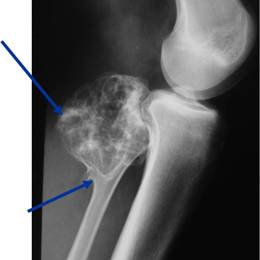

Radiographic imaging is used to help form a diagnosis. These include X-Ray, MRI, CT and Bone Scans.

An example of an Osteochondroma MRI is shown.